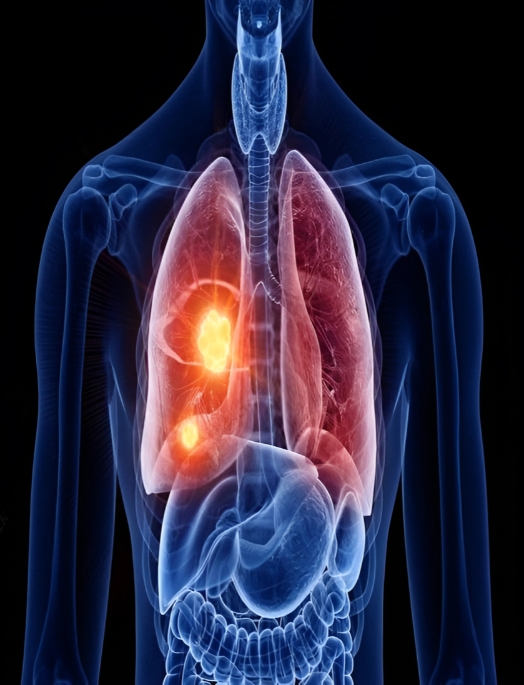

“ Lung cancer begins in the trachea, the bronchus, the major airway, or the lung tissue. A cancer that first develops in the lung is called primary lung cancer. Lung cancer can primarily take any of the following two forms:Lung cancer directly affects your breathing system. It can be deadly if you do not notice it at an early age. But, if you are from Lucknow then no need to be worried about it. For Lung cancer treatment in Lucknow, Dr. Amit Pandey is a well-known oncologist in Lucknow. You can consult him for medical treatment of lung cancer. “